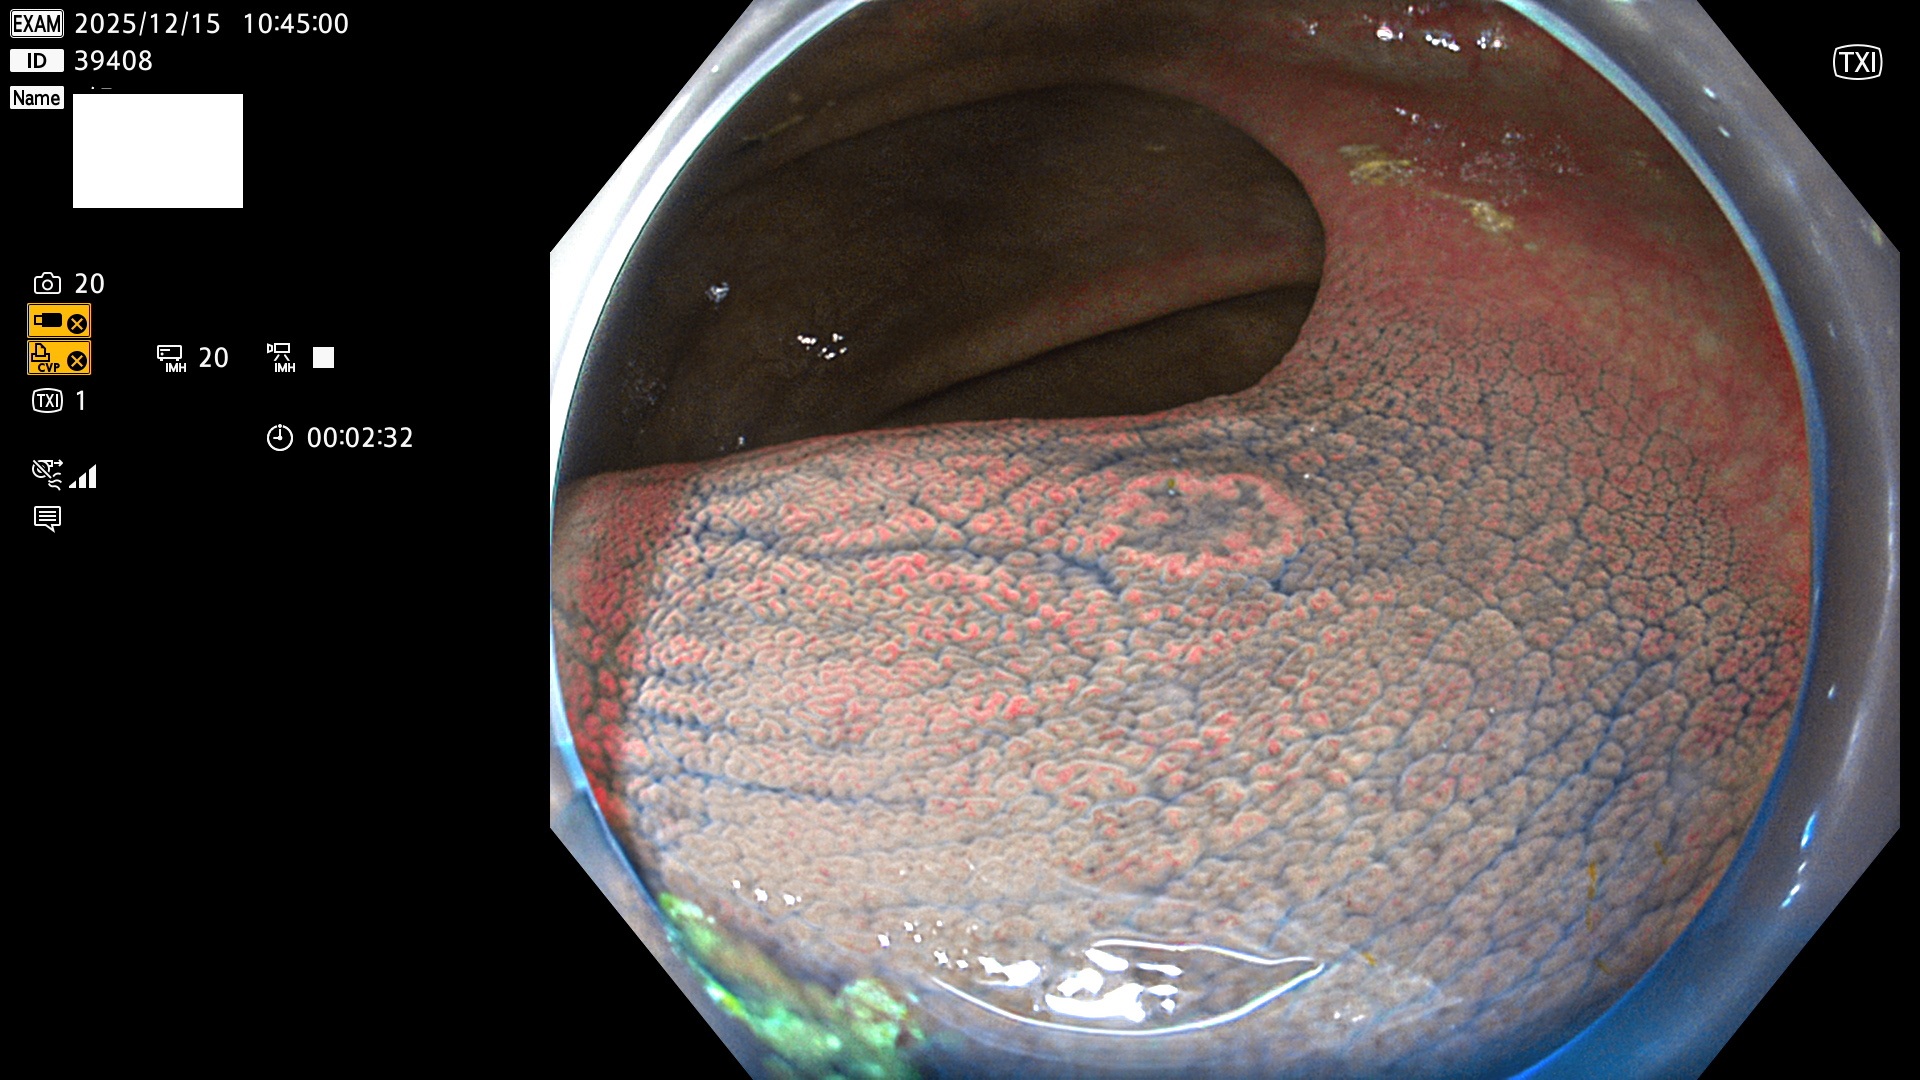

完全に平坦な物をUb、陥凹している物をUcと呼びます。Ubは認識が困難で、Ucはびらん(炎症)と紛らわしいために見落とされやすく、「内視鏡後・大腸癌」の原因になります。

専門的)Uc=De Novo癌? 内視鏡の解像度が低かった時代、このような説もありました。しかし今日の高精度内視鏡では良性の微小なUc型腺腫(APC遺伝子異常の腺腫)が日常的に見つかります。Ucこそが多段階発癌(Adenoma-Carcinoma Sequence)のMain Routeです。

毎週の検査(木・金・土・日)に発見されたUbとUc型・腺腫を、その週の日曜の夜にUPし1週間、提示します。

2025年11月11日〜12月15日の4日間(50件)6個 (Uc_ADR=6個/50人=12%)